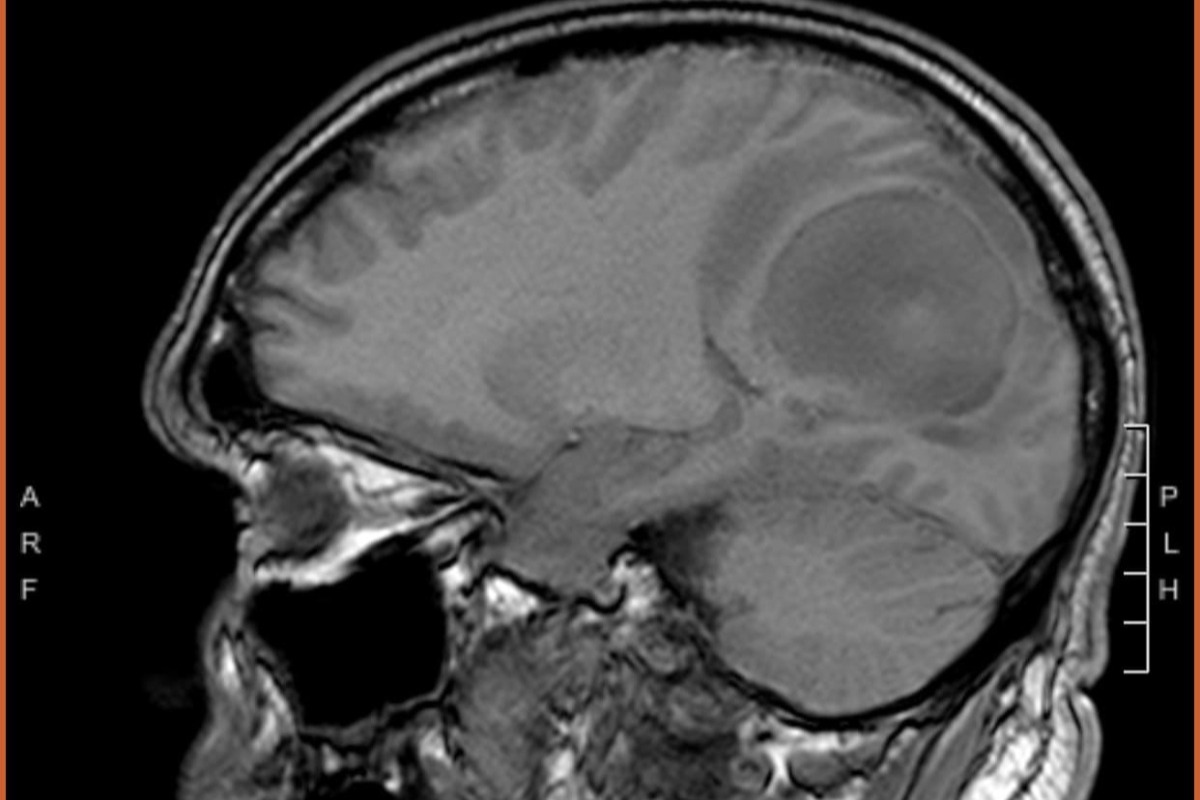

Eric's brain scan.   Mass is in the upper right.

Eric's imaging, prior to his Wednesday surgery.

Eric's path to diagnosis, surgery, and treatment has been a whirlwind and life altering in a very short period of time.  On Saturday, January 23rd, Yadi took Eric into the ER at Tampa General Hospital, after he had become increasingly confused and was struggling with the loss of vision in his right eye.  He was also experiencing weakness, vomiting spells, and headaches.  They performed an MRI and the results came back showing a very large brain tumor (about the size of a large egg).  After meeting with his neurologist, it was determined that they needed to remove the tumor and surgery was scheduled immediately.  Eric endured brain surgery for over 6 hours and doctors were able to remove the vast majority of the mass.

He was up and walking the day after surgery!  A true warrior!  However, the pathology report revealed the numbing news that the mass was Stage IV, Glioblastoma, one of he most aggressive forms of brain cancer.